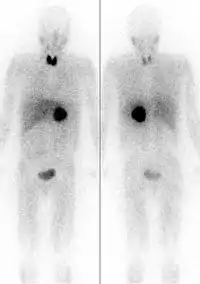

The first functional imaging technique utilized in pheochromocytoma patients was 123I-MIBG scintigraphy (Image Right). Given the compounds similar structure to the catecholamine norepinephrine (secreted by pheochromocytomas), MIBG was well-suited for uptake by most neuroendocrine tumors.[83] Furthermore, if a patient was found to be positive on an MIBG scan, they were eligible for MIBG treatment, offering additional avenues for those suffering from widespread metastatic disease.[84] However, further investigation revealed that while MIBG excelled with adrenal lesions, it was far less superior in patients with extra-adrenal paragangliomas, particularly with specific genetic variants like succinate dehydrogenase subunit X (SDHx).[72] As the positron emission tomography scans were developed, MIBG has slowly loss its favor for the pheochromocytoma patient.[72]

Of the four above mentioned modalities, 18F-FDG PET is the most common and readily available functional imaging technique at most hospital systems, but the least-specific to neuroendocrine tumors (Image Left). In 2012, over 200 patients participated in a trial that compared the current gold standard of the time (MIBG/CT/MRI) to the novel FDG PET. Compared to its functional counterpart, FDG outperformed MIBG in detecting soft-tissue and bone metastases with a higher specificity in patients with biochemically active tumors.[72]